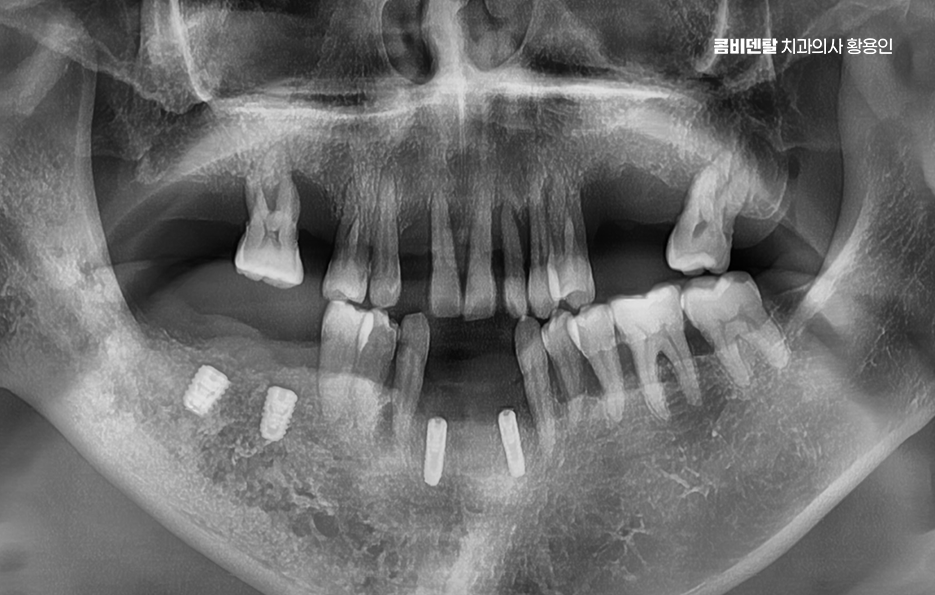

50대임플란트 치료는 시작 전에 정밀한 진단이 선행되어야 하는데 단순히 빈자리만 보고 이 자리에 임플란트를 하나씩 심는 방식이 아니라 턱뼈 상태, 잇몸 높이, 씹는 힘의 분포, 전체 교합의 불균형까지 전부 고려해야 안정적이고 오래 가는 치료가 될 수 있어요

그래서 CT 촬영으로 턱뼈의 두께, 밀도, 신경 위치를 정밀하게 확인하고 각 임플란트의 위치와 각도를 계획해야 하며 50대는 전신 건강 상태도 함께 고려해야 하는데 당뇨, 고혈압, 골다공증 같은 만성 질환이 있는 경우에는 임플란트 치료 시 잇몸 치유 속도나 골융합 반응이 다를 수 있기 때문에, 반드시 의료진과의 충분한 상담이 필요하고 약물 복용 여부나 치유 능력 등을 고려해 치료 시기와 방식을 1:1 맞춤형으로 계획하실 필요가 있어요

군데군데 빠진 치아를 전부 임플란트로 하나씩 심을 수도 있지만, 꼭 그럴 필요는 없으며 예를 들어 어금니 3개가 빠졌다면 3개를 다 심지 않고, 2개만 심고 그 사이를 브릿지로 연결하는 방식도 가능한데 이러한 치료 계획은 단순히 효율성이나 경제적인 측면만 따지는 것이 아니라 각 개인의 잇몸 뼈 상태와 식립 위치, 각도 그리고 사후관리까지 종합적으로 판단해야 하기 때문에 경험 많은 치과의사와 함께 충분한 상의 후에 결정해야 하는 거예요